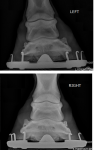

I 5-stage vetted her and she "passed", but with some comments that she has slightly bad conformation on one of her forelegs. As you can see in the x-ray attached, the bones in her lower left leg are a bit bent.

The vet wasn't too concerned about it - but did say it's not ideal and could wear down those joints more than usual. He also suggested the farrier can make it better.

I 5-stage vetted her and she "passed", but with some comments that she has slightly bad conformation on one of her forelegs. As you can see in the x-ray attached, the bones in her lower left leg are a bit bent.

The vet wasn't too concerned about it - but did say it's not ideal and could wear down those joints more than usual. He also suggested the farrier can make it better.